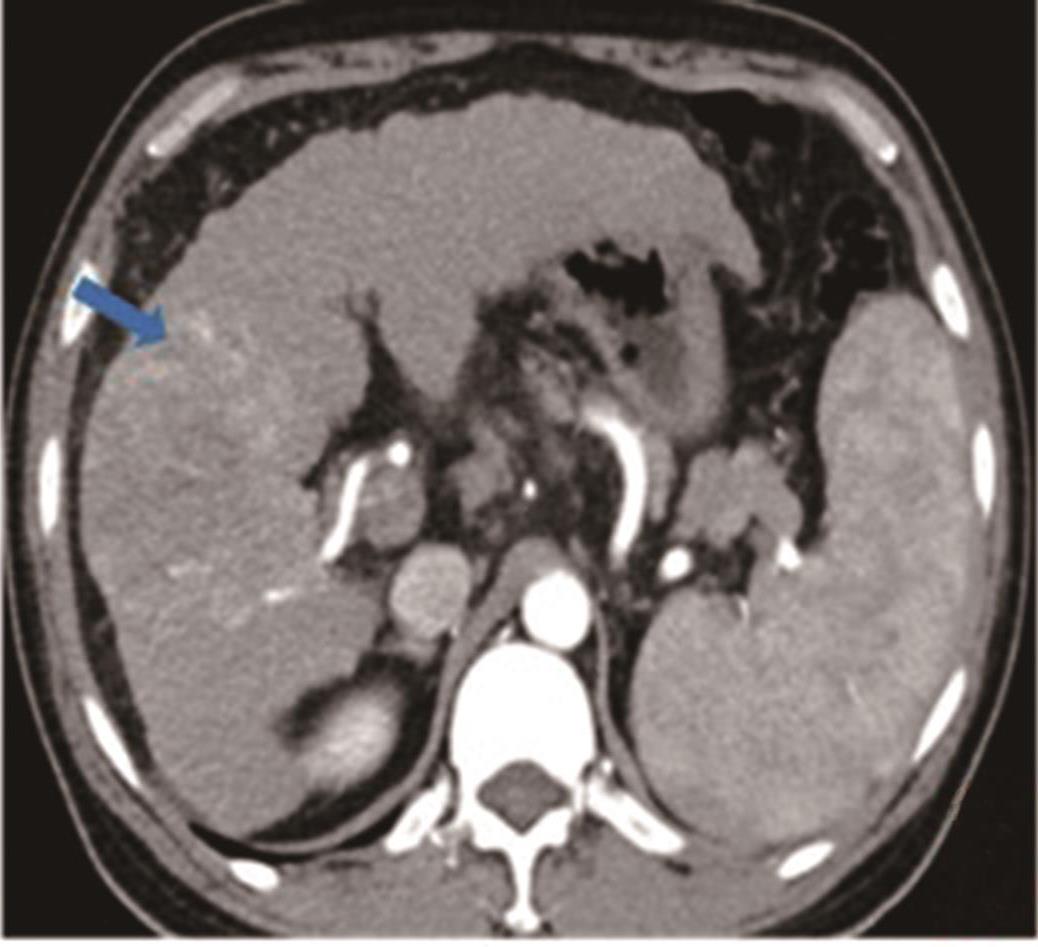

• 探讨增强CT在鉴别胆囊癌侵犯肝脏与肝癌累及胆囊病变中的应用价值

摘要:目的 探讨增强电子计算机断层扫描(computer tomography,CT)在胆囊癌侵犯肝脏与肝癌累及胆囊病变中的鉴别诊断价值。方法 收集2012年2月到2022年2月重庆医科大学附属第一医院115例患者临床及影像学资料,其中胆囊癌侵犯肝脏病例69例,肝癌累及胆囊病例46例,记录性别、年龄、肿瘤大小、肿瘤边界、胆囊形态、肝硬化、胆管扩张、肿瘤内或胆管系统内高密度影、门静脉癌栓、强化方式、强化程度、淋巴结肿大及远处转移共13个观察指标,并进行统计学分析。结果 性别(P=0.007)、年龄(P=0.002)、肿瘤大小(P=0.003)、肝硬化(P<0.001)、肿瘤内或胆管系统内高密度影(P=0.013)、门静脉癌栓(P<0.001)、强化方式(P<0.001)及淋巴结肿大(P=0.034)有统计学差异。通过回归分析筛选出年龄(敏感度为0.812,特异度为0.457)、肿瘤大小(敏感度为0.630,特异度为0.696)、门静脉癌栓(敏感度为0.326,特异度为0.957)、淋巴结肿大(敏感度为0.681,特异度为0.522)为显著分类指标,联合4个观察指标的参数绘制受试者工作特征(receiver operating characteristic,ROC)曲线,曲线下面积(area under the curve,AUC)为0.770,敏感度为0.674,特异度为0.826。结论 增强CT在鉴别胆囊癌侵犯肝脏与肝癌累及胆囊病变时,性别、年龄、肿瘤大小、肝硬化、肿瘤内或胆管系统内高密度影、门静脉癌栓、强化方式及淋巴结肿大有鉴别价值,同时结合年龄、肿瘤大小、门静脉癌栓及淋巴结肿大有助于提高鉴别诊断能力。